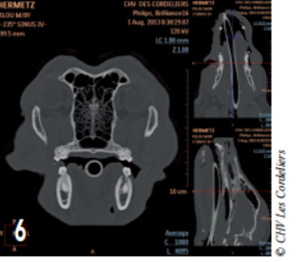

Le scanner a révélé la présence d’une lyse osseuse de l’os alvéolaire mandibulaire s’étendant de la racine dorsale de la carnassière jusqu’à la racine caudale de la deuxième prémolaire (photos 2 à 6).

Photo 6 : La lyse osseuse est visible au niveau de la deuxième molaire.